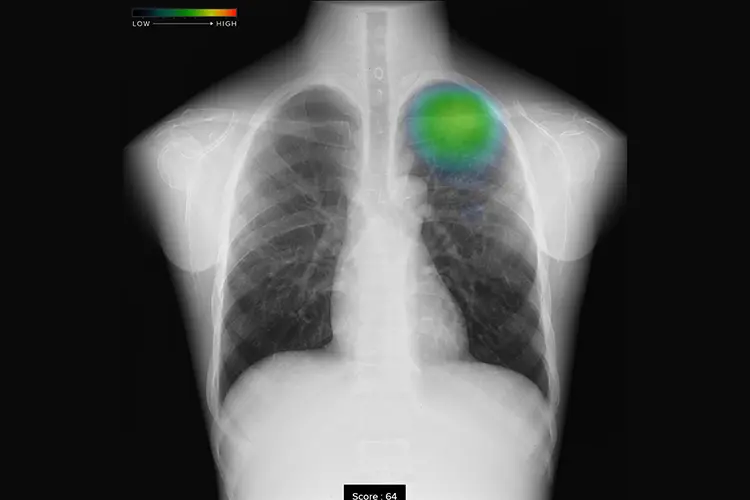

胸部X線画像病変検出AI

FUJIFILM CXR-AID近年、AIは目まぐるしく発展しています。当院でも、胸部レントゲン用のAIシステムを導入し、レントゲンの異常を自動で検出し、医師の読影とAIの判断を合わせてより正確に診断することができます。